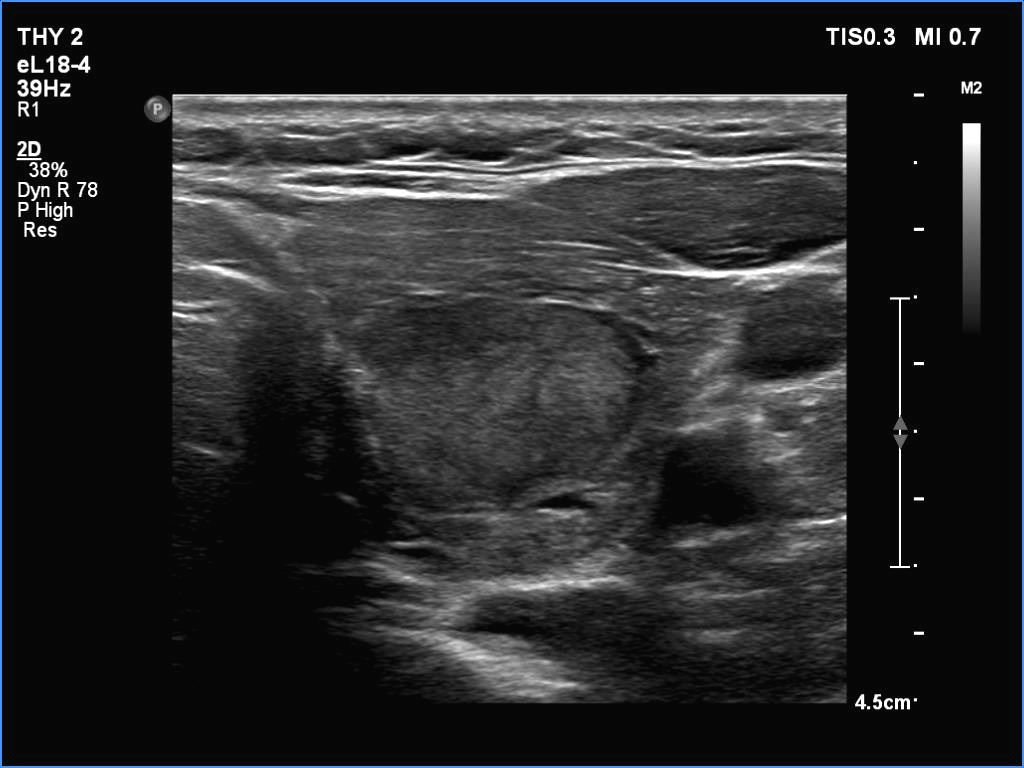

Ultrasonography. The thyroid was partly minimally/moderately, partly very hypoechoic. There was a nodule in the middle of the left lobe. It was lighter than the extranodular part but darker than a normal, healthy thyroid.